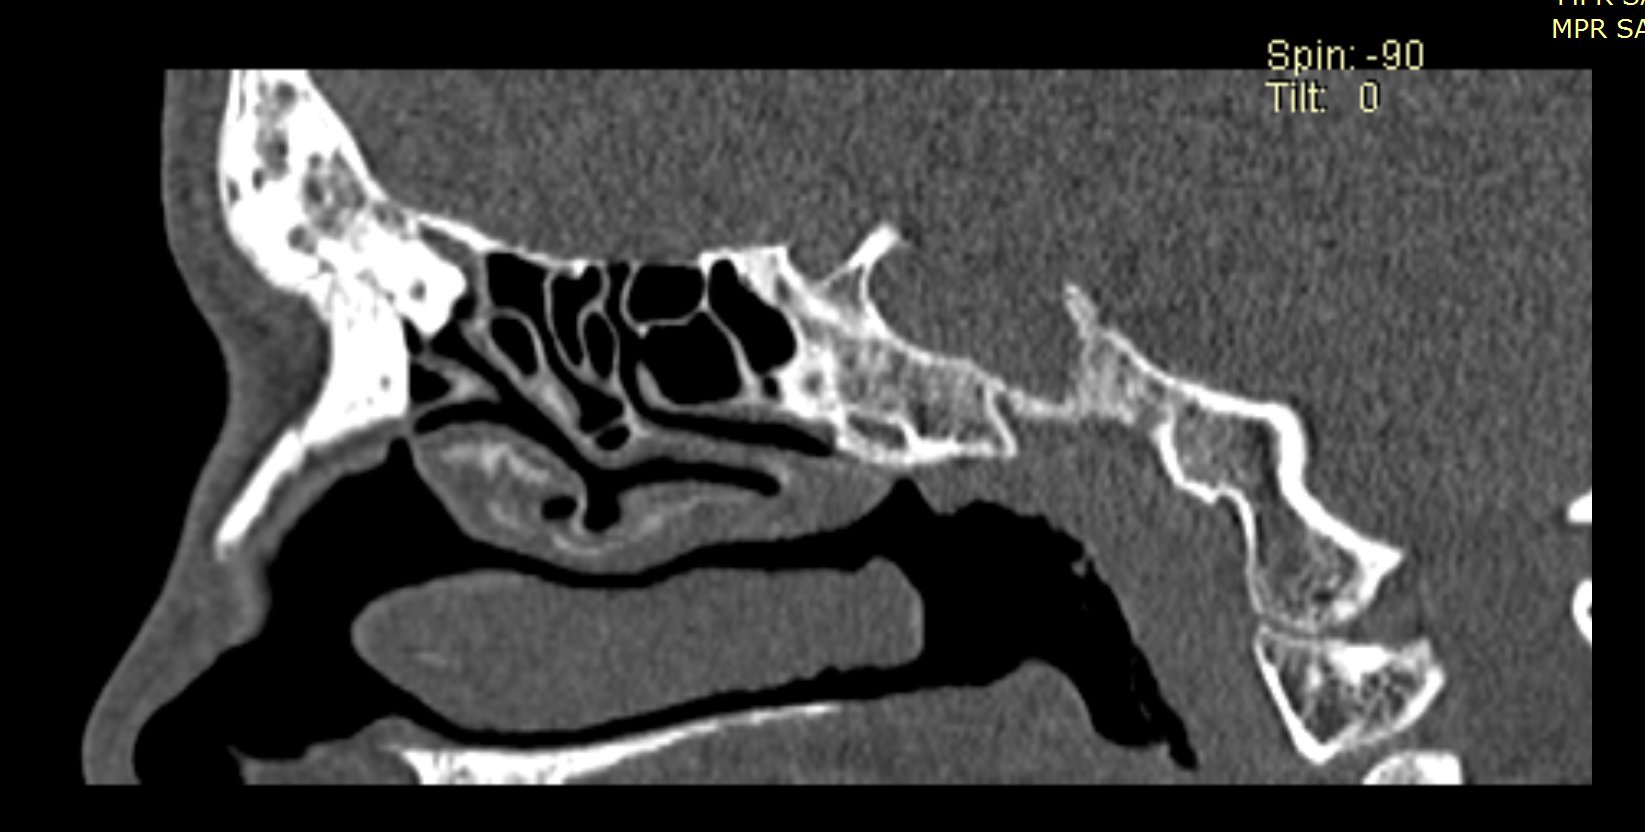

Examenul clinic ORL și examenele imagistice complementare (CT, RMN sinusuri paranazale) pun în evidență o formațiune tumorală osteogenică a sinusului frontal drept, protruzivă în unghiul supero-intern al orbitei, extinsă medial către sinusul frontal stâng.

- Se expune formațiunea tumorală osteomatoasă care ocupă în totalitate cavitatea sinusală frontală dreaptă, se extinde către sinusul frontal controlateral și către orbita dreaptă, creând presiune pe atmosfera celulo-grasoasă periorbitară la nivelul unghiului supero-intern OD. Formațiunea este intens aderentă la nivelul peretelui sinusal postero-superior. Aceasta prezintă două zone de consistență diferită.